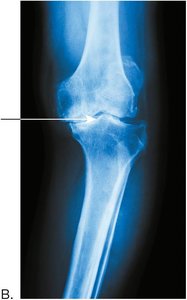

Joint Diseases

Osteoarthritis and Rheumatoid Arthritis

Osteoarthritis is a chronic inflammatory disease of joints, especially weight-bearing joints, characterized by cartilage degeneration and bone spur formation. Rheumatoid arthritis is an autoimmune disorder causing inflammation and deformity of joints, most often in the hands and feet.

Normal knee joint x-ray Knee joint with osteoarthritis, showing narrowed joint space and malalignment Hands with severe joint deformities from rheumatoid arthritis